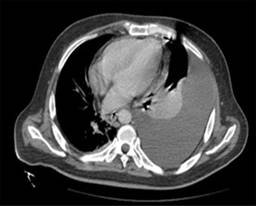

Se realizó una radiografía anteroposterior (AP) de tórax, en la cual se visualizó un derrame pleural izquierdo que cubría más de 50%. La tomografía computarizada mostró una importante cantidad de líquido en el espacio pleural izquierdo que condicionó una atelectasia pasiva del lóbulo inferior (Figura 1); el hígado se encontró con densidad heterogénea con incremento del lóbulo hepático izquierdo secundario a la presencia de una lesión heterogénea hipodensa con bordes lobulados, que muestra un reforzamiento periférico y de algunos septos internos, la cual abarca los segmentos II, III, IVa y IVb midiendo aproximadamente 20 × 14.5 × 12.5 cm (Figura 2), condicionando desplazamiento posterior y compresión del estómago y del páncreas y desplazamiento caudal de las asas intestinales (Figuras 3 y 4). En el polo inferior del lóbulo hepático derecho adyacente al segmento IV se identifica una lesión de aspecto quístico homogéneo con reforzamiento periférico tras la administración de contraste intravenoso, midiendo en sus ejes mayores 25 × 27 × 13 cm. Como manejo inicial se le colocó una sonda Foley y sonda nasogástrica presentando gasto de características gástricas (30 ml). Se colocó un catéter central, verificado por radiografía. Se solicitaron estudios de imagen. Se le indicó ayuno, se inició fluidoterapia, antibioticoterapia con ceftriaxona y metronidazol, manejo del dolor, control glucémico y protector gástrico. Al visualizar la imagen del derrame pleural izquierdo, se decide realizar una toracocentesis, obteniendo exudado espeso de aspecto “chocolatoso”. Al momento de contar con la tomografía se inicia tratamiento quirúrgico urgente.

Figura 2: Tomografía axial computarizada sin contraste a nivel del bazo en la que se observa una imagen hipodensa, multilobulada.